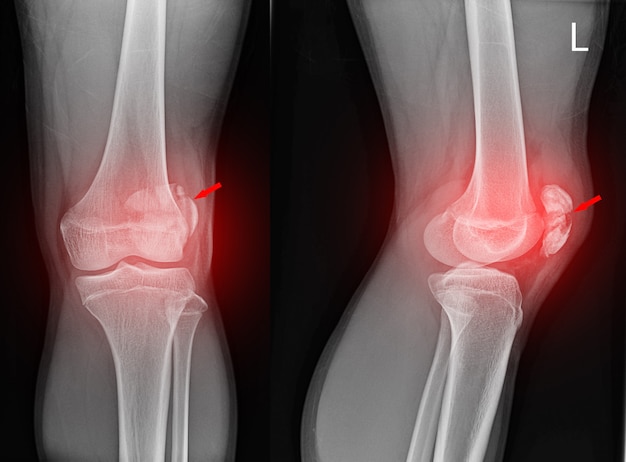

Рекурвация коленного сустава: рентгеновские снимки и объяснения